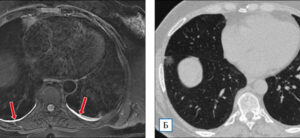

Хронический облитерирующий бронхиолит у детей и взрослых

Бронхиолит — тяжелая патология дыхательной системы. Часто развивается у детей в возрасте до одного года. Ежегодно во всем мире регистрируется 150 миллионов случаев этого заболевания, которое может быть острым или хроническим. Облитерирующий бронхит — это заболевание, которое сопровождается нарушением воздушного потока в дыхательных путях, что ухудшает прогноз. Общая информация Бронхит — воспалительная патология дыхательных путей, …